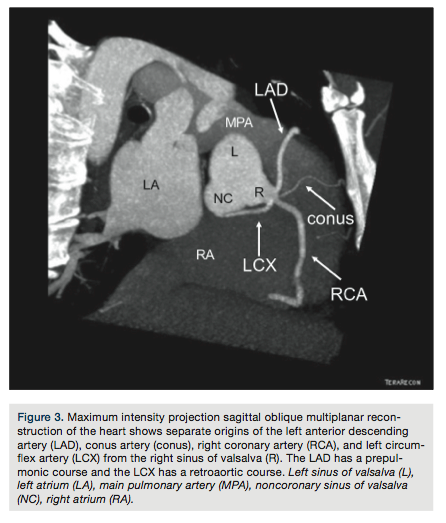

abnormal electrocardiogram (ECG) was referred for further evaluation. Review of his ECG showed 2-mm ST elevation in leads V2 and V3, and 1-mm ST elevation in leads V4-V6. Transthoracic echocardiography showed only mild global left ventricular (LV) hypokinesis. Subsequent coronary angiography (Figure 1) revealed a single common coronary artery (SCA) arising from the right coronary cusp with no significant obstructive disease and a dominant right coronary artery (RCA) that wrapped around the left ventricular apex. Computed tomography coronary angiography (Figures 2-5) confirmed the right coronary cusp origin. The left anterior

descending coronary artery (LAD) was shown to course anterior to the pulmonary artery. The left circumflex and RCA followed a relatively normal course; the RCA was confirmed to be large and to cover an extensive part of the inferior and apical left ventricular walls.